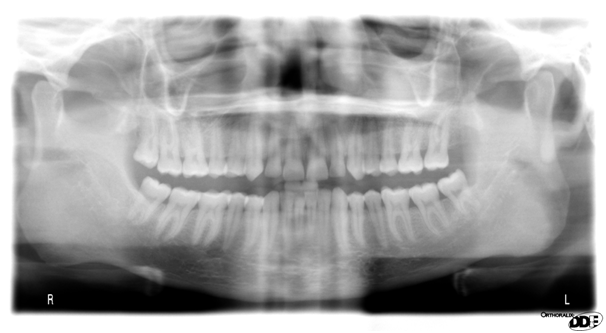

A 22 Yemeni male patient presented to the College of Dentistry clinics at the University of Dammam seeking cosmetic treatment with a chief complaint “I want to improve the way my teeth look " He reported no significant medical history. Patient has never been into the dental clinic. He stated his deciduas teeth were normal and his whole village complains of darkened teeth (brownish). A panoramic x-ray (Figure 1), intraoral pictures (Figures 2−6) as well as study casts were taken to diagnose the case (Figure 7). Upon examination, the patient was found to suffer from severely generalized discoloration of permanent teeth and moderate dental attrition resulting in shortening of the vertical dimension of occlusion (VDO). A class I occlusion with class I canine relation was present, with an over-bite of 4mm and an overjet of 4mm. The upper lip seems stretched with dropping mouth angles. The patient suffers from generalized marginal chronic gingivitis with no mobility or furcation involvement noticed. The treatment plan started with plaque control measures were conducted as well as patient education. The patient's esthetic problem caused by Fluorosis both teeth staining and facial appearance and occlusion. The treatment options available range from bleaching, porcelain veneers, full coverage ceramic crowns or porcelain fused to metal crowns. Due to the Fluorosis severity, the bond strength of the adhesive agent was questionable that eliminated the veneers option. Bleaching when tried had minimal effects. Finally, porcelain-fused to metal (PFM) crowns were selected to restore esthetics of anterior teeth, while posterior gold crowns were chosen to raise the occlusion posterior by 2mm. Treatment options were discussed with the patient who consents to the treatment plan.

Figure 2 Pre op front view.